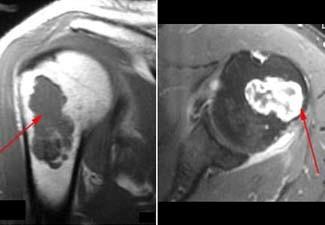

Other imaging tests. Your doctor may order a computerized tomography (CT) or magnetic resonance imaging (MRI) scan to help further evaluate your tumor. These scans give a more complete picture of the bone around the tumor. If the tumor has turned into a malignancy, the scans may show bone erosion, bone inflammation, or a mass growing outside the bone.

Characteristics of a more aggressive tumor or a malignant chondrosarcoma include:

- Thickening of the bone's outer cortex

- Reactive bone growth on the outer surface of the bone

- Destruction of the bone by the tumor

- Soft-tissue mass expanding from the tumor